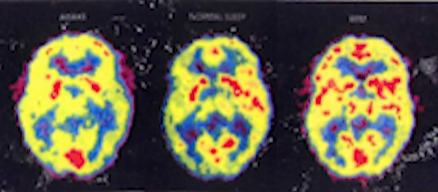

- 睡眠是身体在休息,大脑在工作

图9-1 三张图分别是:清醒时、睡眠时、做梦时 - 睡眠时大脑在补充神经传导物质

- 做梦的时候大脑活化得非常厉害,它是在把白天发生的事情拿出来重新整理